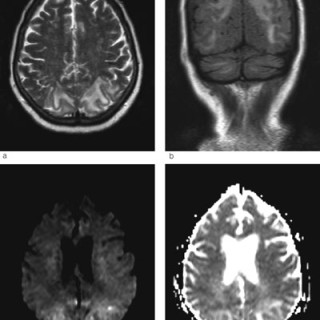

En 40 år gammel kvinne ble innlagt i medisinsk avdeling til utredning for anemi (1). Hun hadde tidligere vært frisk, men hadde de siste månedene før innleggelsen følt seg tiltakende slapp og tungpustet. I en periode hadde hun hatt rikelige og langvarige menstruasjoner. Av egen lege hadde hun fått jerntabletter, men hadde likevel Hb 6,8 g/100 ml. Ved innleggelsen var pasienten i noe redusert allmenntilstand, blek, men med uanstrengt respirasjon. Organstatus var normal, bortsett fra at man mente å kunne palpere uterus. Blodprøvene viste følgende verdier: Hb 6,5 g/100 ml, leukocytter 6,0 · 10⁹/l...